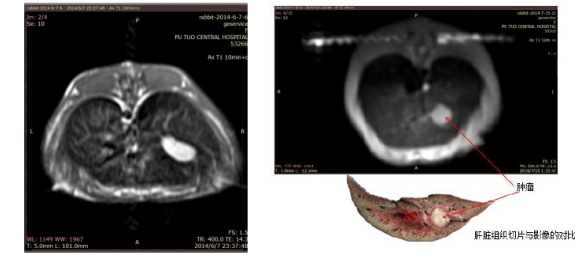

肝臟腫瘤造影: